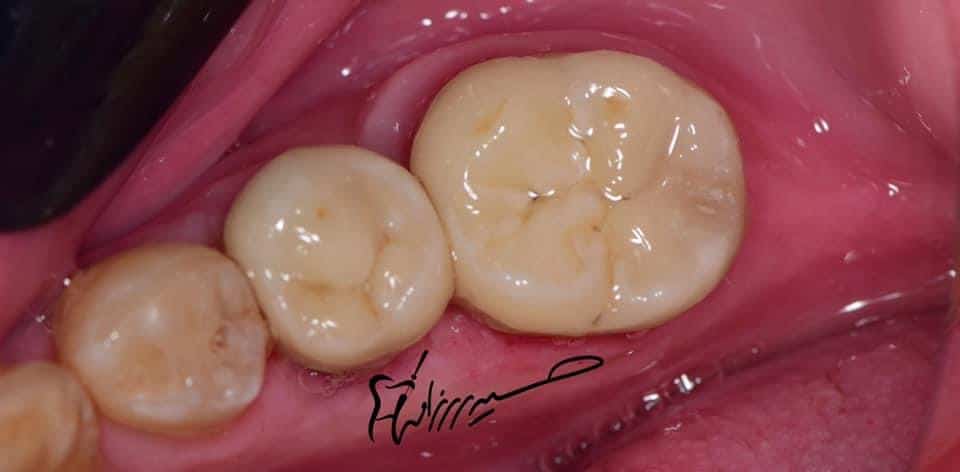

Final situation

Lateral view

Before and after